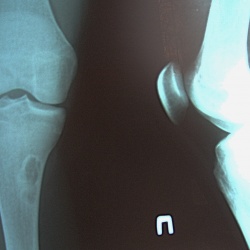

пришла в кабинет после травматолога. Занимается футболом. Была травма и после этого, около месяца назад почувствовала боли в этом коленном суставе. Честно говоря на ум конкретного ничего не пришло...